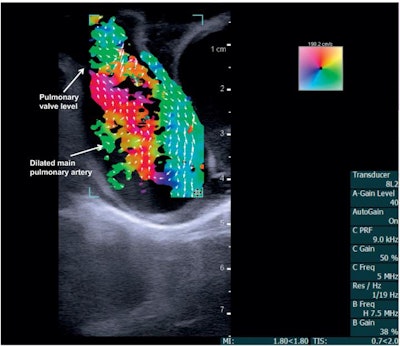

The team used an ultrasound scanner with vector flow imaging to image the hearts of two three-month-old babies, one with a healthy heart and one with congenital heart disease. The technology allowed for complete transthoracic imaging of tissue and blood flow at a depth of 6.5 cm; abnormal flow and cardiac anomalies were clearly visualized in the child with congenital heart disease.

Vector flow imaging demonstrates swirl of blood flow within the dilated main pulmonary artery of a pig. Image courtesy of Dr. Morten Jensen, PhD."Vector flow imaging technology is not yet possible in adults, but we have demonstrated that it is feasible in pediatric patients," Jensen said in a statement released by the university April 3. "Our group demonstrated that this commercially available technology can be used as a bedside imaging method, providing advanced detail of blood flow patterns within cardiac chambers, across valves, and in the great arteries."